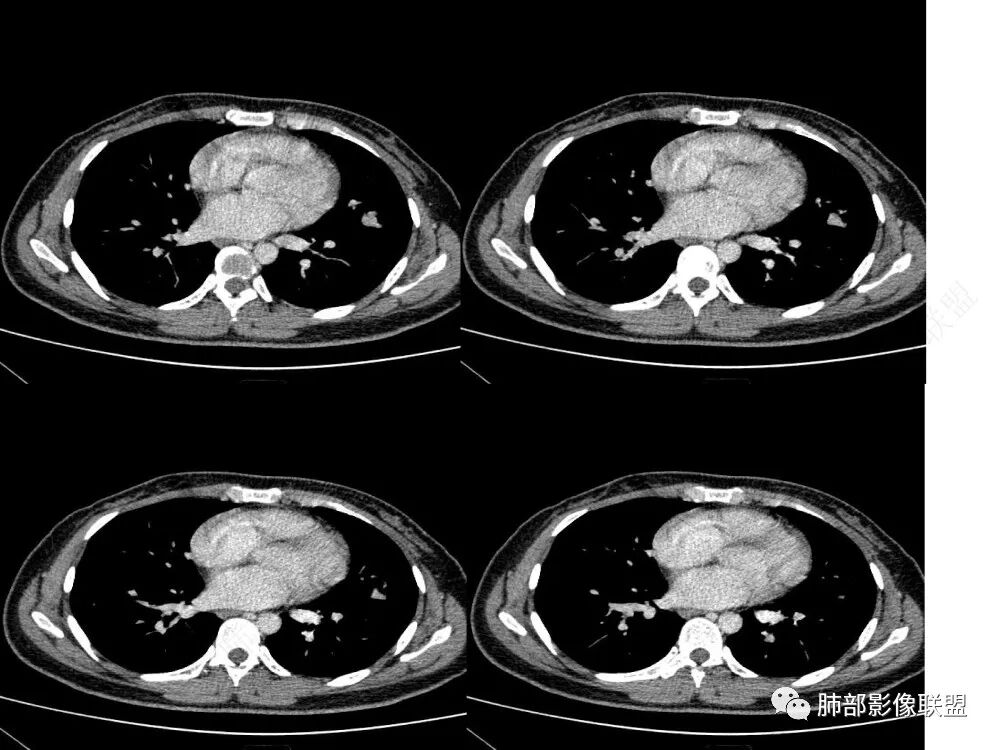

1、临床特点:30岁女性,体检发现肺部结节。

2、影像特点:左肺上叶舌段实性密度结节,边界清楚,略呈不规则三角形,边缘多平直,未见分叶、毛刺及明显收缩。密度均匀,未见钙化、脂肪密度或低密度液化空洞,持续渐进强化。未显示相关支气管及血管出入、血管贴边等。未见明确卫星病灶。双肺门及纵隔未见增大淋巴结。

3、病例小结:年轻女性,体检发现,左肺上叶舌段实性结节,边缘清楚光滑,未见分叶毛刺及收缩,亦未见边界清晰的磨玻璃晕,与支气管血管了无瓜葛等,较为符合的是肺良性结节。

CT:形态:圆形或椭圆形结节,边界清楚,无分叶及毛刺、无胸膜凹陷征及血管集中等恶性征象,无卫星病灶,周围无纹理增多及粘连等;大小:平均直径3cm,从<1cm到>10cm均有报道;密度:均匀、软组织密度,偶有出血、囊变、钙化;强化方式:多为均匀明显强化,少数不均匀强化;其它特殊征象:血管贴边征 、空气半月征 、晕征,偶见纵隔淋巴结肿大。